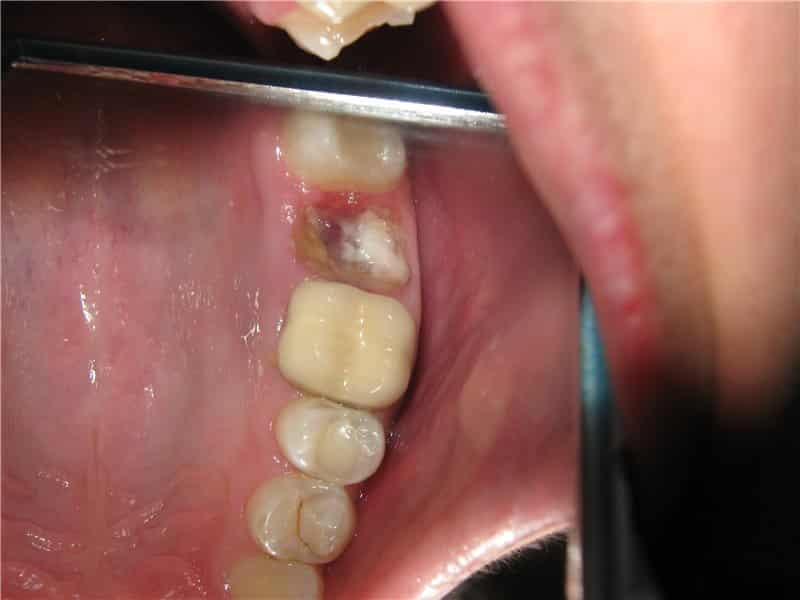

Нагноение после удаления зуба может указывать на различные постоперационные осложнения. К ним относятся:

- Альвеолит. Обычно он проявляется покраснением и отечностью лунки, а также острыми болями, кровотечением и образованием гнойных выделений. Альвеолит может сопровождаться ухудшением общего состояния, включая повышение температуры, дрожь, головные боли и чувство слабости.

- Флюс. Это воспаление надкостных тканей в области поврежденной десны. Обычно инфекция проникает в лунку после удаления зуба. Флюс сопровождается острой болью, отеком и припухлостью, а также повышенной температурой. Диагностика флюса может быть затруднена, поэтому рентгенография может оказаться полезной.

Важно помнить, что при ослабленном иммунитете даже простое удаление зуба может значительно увеличить риск заражения лунки альвеолитом. Последствия этого можно увидеть на фотографиях гноя в лунке после удаления зуба.